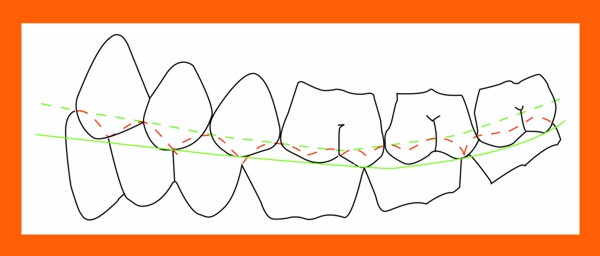

Primera Parte RESUMEN: La alta complejidad inherente a los procedimientos de Rehabilitación Oral, obligan al profesional que la ejerce a basarse en parámetros multidisciplinarios, a veces lo suficientemente intrincados que hacen imposible la práctica de la misma, sin la presencia en su mente de una clara concepción de la Oclusión. The extreme complexity of Oral Procedures, make it imperative for the working professional to rest on multidisciplinary parameters, sometimes so complex that make impossible its practice without the presence of a clear idea of Oclusion. DESARROLLO Suele ser sumamente árido el abordaje de un tema como Oclusión, desde la perspectiva de nuestro diario trabajo ,con todo el strees que este conlleva, con toda la lucha que significan citas, honorarios, diferentes personalidades de los pacientes, inquietudes de los mismos, etc. «LA MEJOR OCLUSIÓN ES LA QUE TIENE LA MEJOR DESOCLUSIÓN» Básicamente, podemos como desde hace ya muchos años se viene haciendo; clasificarlos en: A)Determinantes Posteriores (fijos) Más contemporáneamente, en: I-Mecanismos Primarios: A.T.M. GUIA ANTERIOR INCLINACIÓN DEL PLANO OCLUSAL CURVA SAGITAL DE SPEE FORMA DE LA ARCADA III-Mecanismos Elementales CRESTAS TRIANGULARES INTERNAS Analicemos cada uno de ellos: Es evidente, que la reproducción de las características de la A.T.M., en nuestro aliado fundamental, el Articulador; es imprescindible. Partiendo de la premisa de obtener una OCLUSIÓN MUTUAMENTE PROTEGIDA, para luego arribar al concepto de OCLUSIÓN MUTUAMENTE COMPARTIDA, concepto este que desarrollaremos durante el transcurso de las distintas entregas, analizaremos cada uno de los FACTORES DETERMINANTES DE LA OCLUSIÓN. El primero de ellos, por ser fijo e invariable, solo diremos que: son sus INCLINACIONES PLANARES, o sea : A-INCLINACIÓN DE LA TRAYECTORIA CONDILEA C-BENNET INMEDIATO articuladores totalmente ajustables) D-DISTANCIA INTERCONDILAR. En cuanto a la GUÍA ANTERIOR, mecanismo primario y por supuesto anterior, provee al cuerpo mandibular; del camino a recorrer durante las excursiones protrusivas y lateralidades, a través del vínculo entre las piezas dentarias anteriores, superiores e inferiores. En un corte sagital, podemos observar la relación entre estos donde vemos que se vinculan sin entrar en un contacto franco, sino más bien en una relación de vencindad muy intima a la que llamamos: PUNTO DE ACOPLAMIENTO. Otros factores fundamentales de la GUÍA ANTERIOR son : A-ALTURA FUNCIONAL B-PUNTO DE ACOPLAMIENTO En cuanto a los SURCOS, sabemos que durante una Transtrusión, las cúspides fundamentales generan surcos sobre las piezas que antagonizan. Dichos surcos proveen de una vía de escape a las cúspides antagonistas para evitar colisiones, con las indeseables fuerzas laterales cuya gravedad ya conocemos. MECANISMOS SECUNDARIOS La CURVA FRONTAL DE WILSON, se observa invertida a nivel de los caninos y de los primeros premolares. El PLANO OCLUSAL, en realidad no es ningún plano, sino la sumatoria de muchos MICROPLANOS, los cuales individualmente pueden constituir factores presentes en la OCLUSIÓN, pero auténticos problemas para la DISCLUSIÓN. La CURVA SAGITAL DE SPEE, denominada originariamente de BALKWIL-SPEE, fue concebida como una curva. El cuarto factor SECUNDARIO: el ANCHO DE LA ARCADA, es evidente que variando los ejes de rotación , alrededor de las diferentes distancias ;cambiará la dirección de los escapes (surcos), de los elementos que en el se muevan (cúspides). MECANISMOS ELEMENTALES Los CUATRO NIVELES DE OCLUSIÓN y las CRESTAS TRIANGULARES INTERNAS, constituyen de por si, la herramienta ejecutora de las funciones gnáticas. A- ELEVACIONES 1-Puntas Cuspídeas B-DEPRESIONES 1-Fosas SURCOS DE DESARROLLO De las CRESTAS TRIANGULARES INTERNAS, acentuamos su importancia en ellas dado que son las efectoras finales de la molienda, y su triangularidad debe tener su base partiendo del surco y su vértice terminando en la Punta Cuspídea, condición importante para evitar colisiones durante la transtrusión (movimiento de lateralidad ). EFECTOS DE LA VARIABILIDAD DE LOS FACTORES DETERMINANTES DE LA OCLUSÍON Cada uno de los determinantes influye aumentando o disminuyendo tanto la DESOCLUSIÓN como la ALTURA CUSPÍDEA INCLINACIÓN DE LA TRAYECTORIA SAGITAL INCLINACIÓN DEL PLANO OCLUSAL RADIO DE CURVATURA DE LA ÁNGULO DE LA TRAYECTORIA ALTURA DEL PUNTO DE LATERO SURTRUSIÓN / MOV. DE BENNET INMEDIATO CURVA FRONTAL DE WILSON SURCOS BIBLIOGRAFÍA Dibujos y esquemas tomados del libro: Oclusión Orgánica…un camino hacia la Rehabilitación Oral. 1)William Mc Horris,B.S.,D.D.S. Oclusión. Con especial énfasis sobre :El rol funcional y parafuncional de los dientes anteriores. 2)Von Spee , Craff(Anatomista alemán, describió la curva de compensación de la articulación de molares y premolares).CURVA DE SPEE 1.89 3)Stuart,D.»Some aspects of the inervation teeth.»Procedings of Royal Society of Medicine.20:1675,19274)Muhleman,H. y Savdir,S»Tooth movility-its causes and significance»Journal of Periodontology ,36:153,Marzo ,Abril,1965. 4)Muhleman,H. Y Savdir,S»Toothmovility its causes and significance» Journal of Periodontology,36:153,marzo,abril,1965. 5-Oclusión y Diagnóstico en Rehabilitación Oral. 6-Anatomia Odontológica. -A contribution to the study of the movementes of the mandible. 8-Celenza F.W, Nadeskin J.F.,Oclusión.Situación actual. 9-D´Amico 10-Dawson P.E. 11-Huffman -Regenos. 12-Hobo S.-Takayama H.A. 13-Lucia V.O 14-Mc Horris. 15-Mc Horris. 13-Posselt U. 16-Stuart C. 17-Vartan Veshnilian

Es recta en el segundo premolar y comienza a ser de concavidad superior a la altura del primer molar, acentuándose hacia atrás para terminar concibiéndose al cóndilo como un cuarto molar.

Sin embargo, si observamos con atención una vista sagital, veremos como la cúspide distal del primer molar; desciende, constituyendo hasta la misma una auténtica recta, y a partir de ella una curva que asciende hasta la cúspide distal del tercer molar.

Se ha dicho, que dicha cúspide descendente, constituiría una mecanismo SUPLETORIO de DESOCLUSIÓN, en el caso de fallar la DESOCLUSIÓN CANINA.